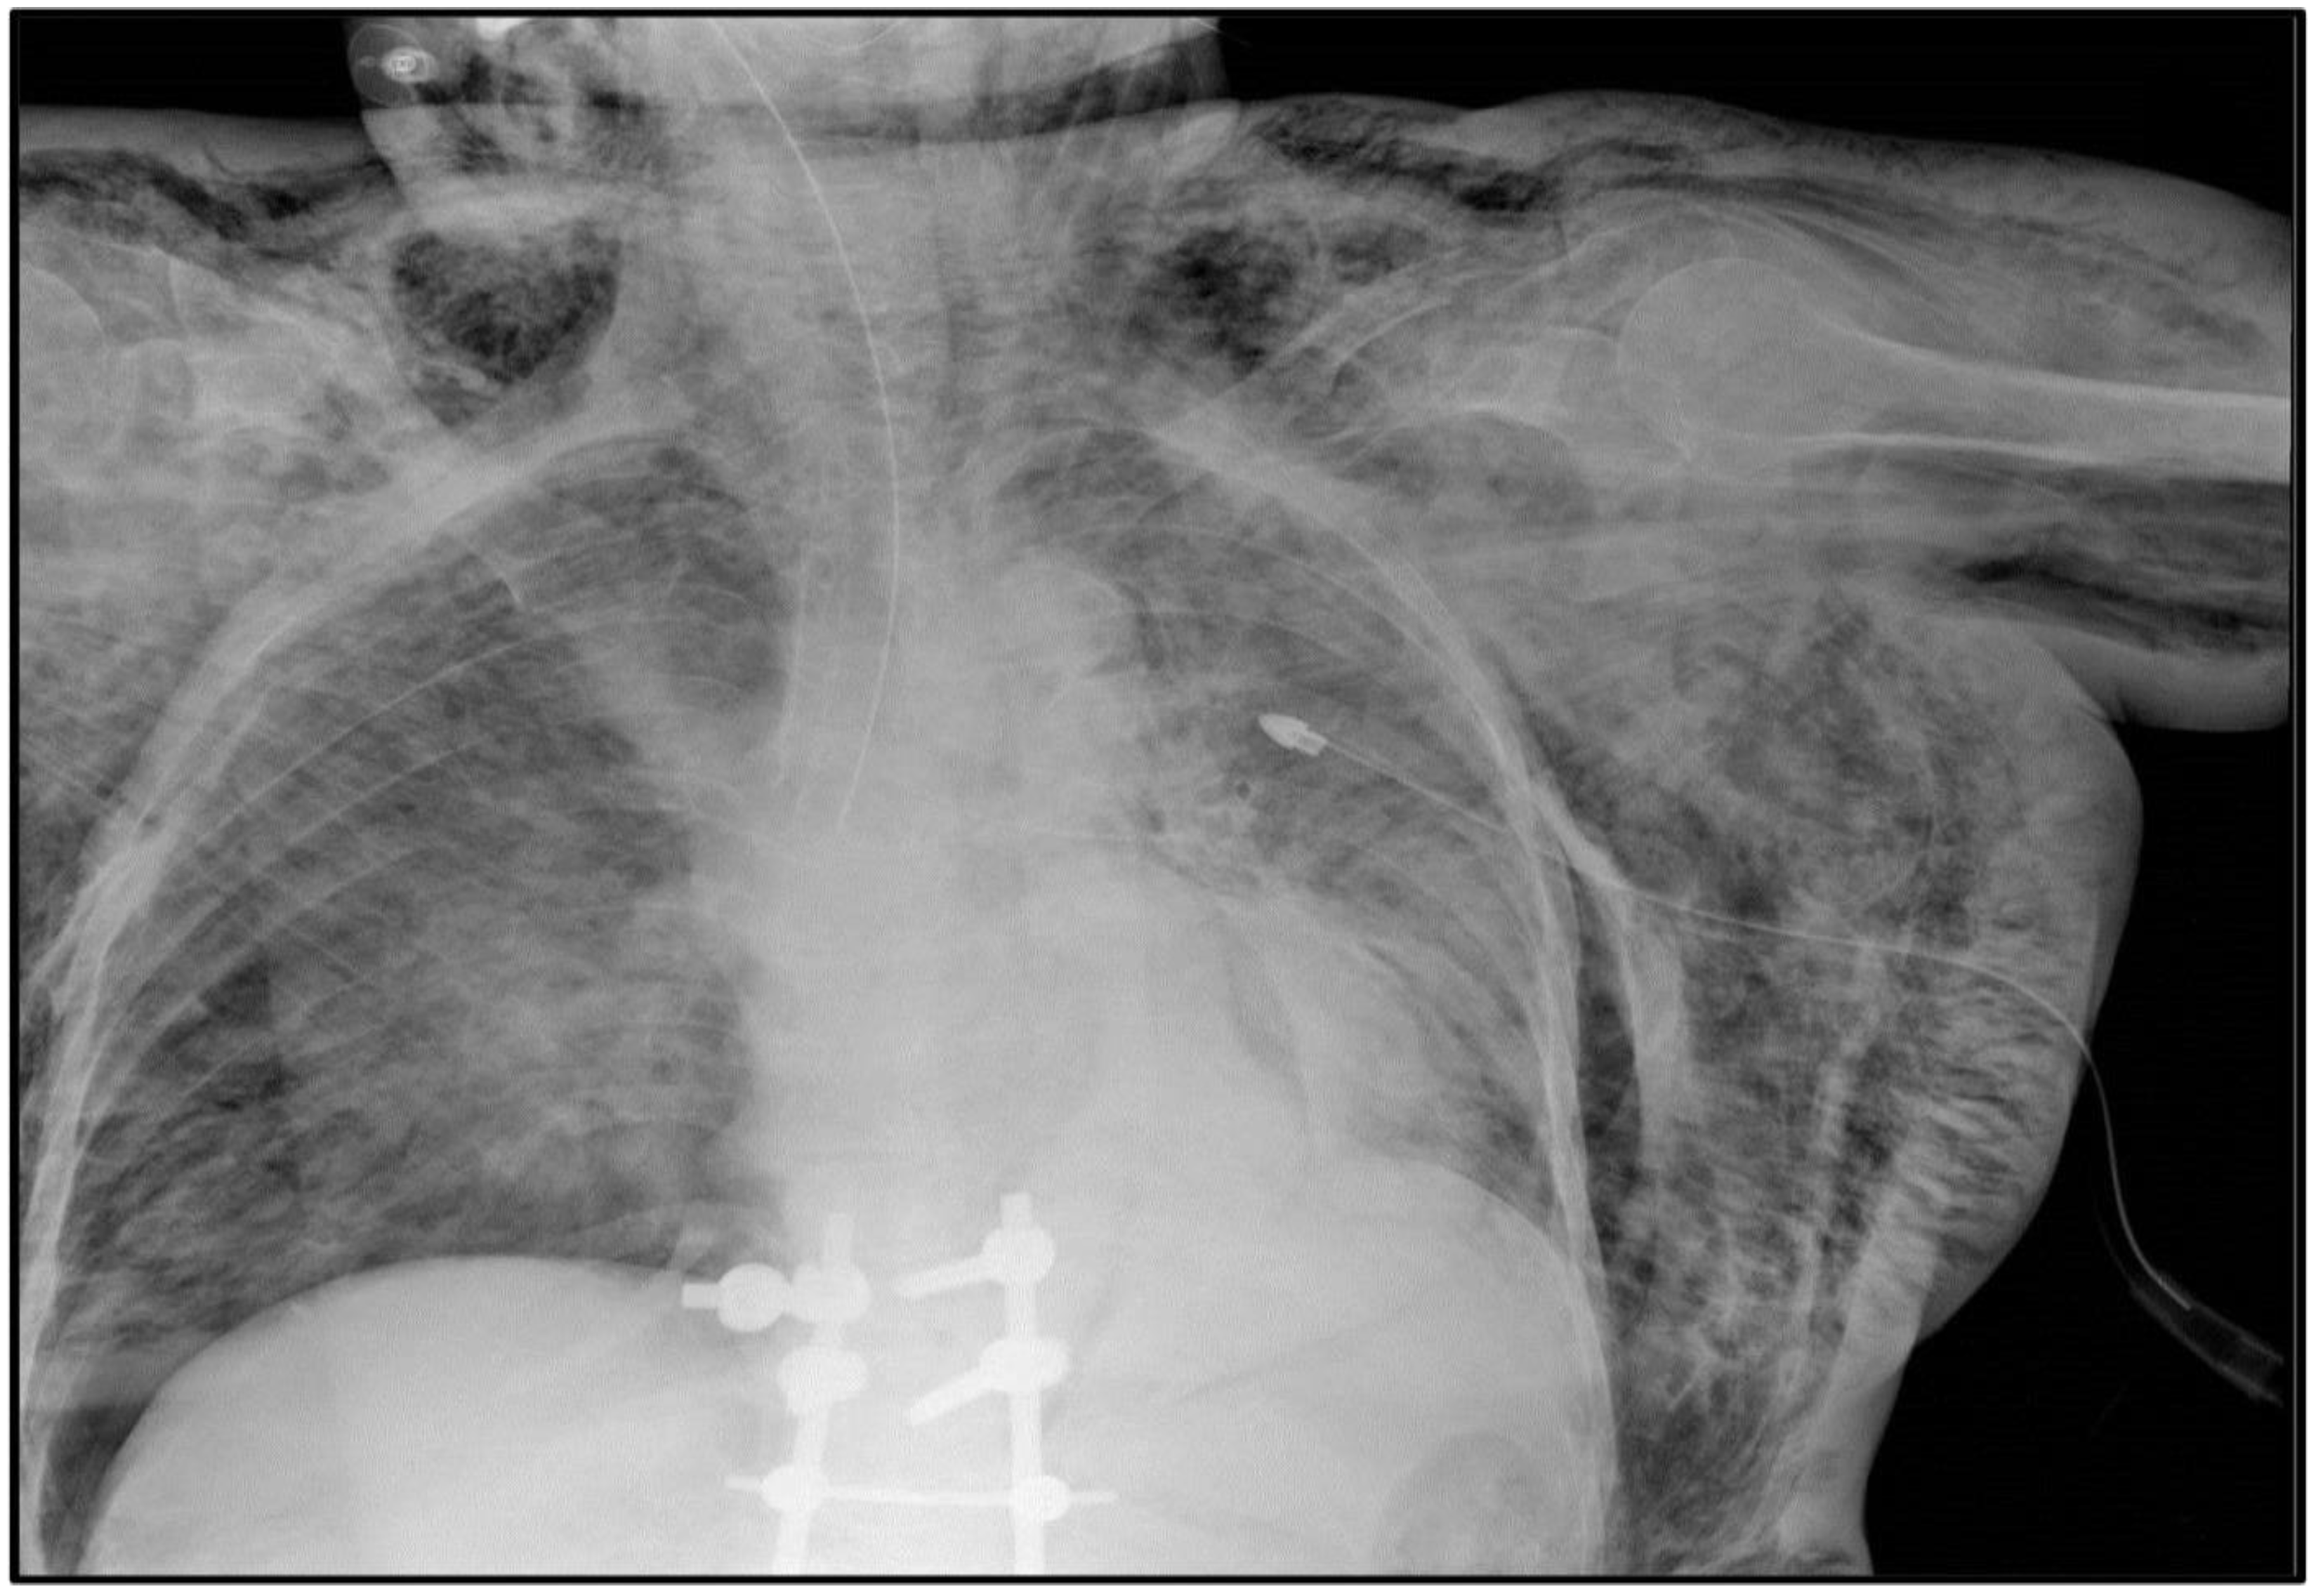

2.1. Case #1